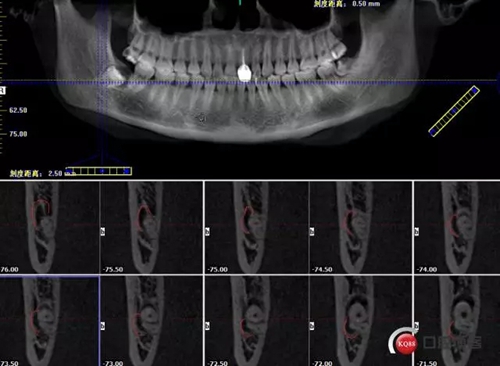

超低位阻生齒緊貼神經(jīng)管伴囊腫

術(shù)前曲面斷層

牙齒上1/3CT切片,神經(jīng)管在下方

牙齒中1/3神經(jīng)管偏頰側(cè)

牙齒下1/3神經(jīng)管在頰側(cè)

術(shù)前分析:1.冠部骨阻力2.近中阻力